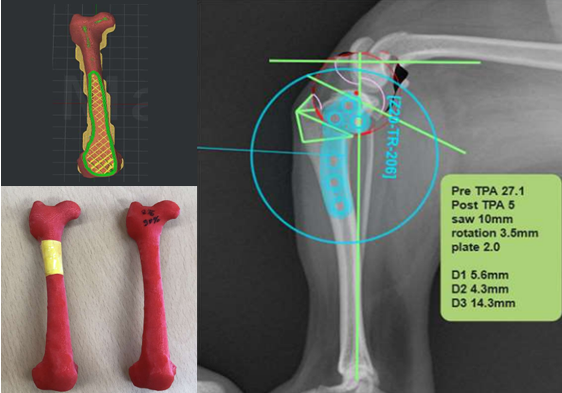

영상 장비를 활용한 진단

방사선 촬영(X-ray), 초음파, CT 등 다양한 영상 장비를 활용하여 진단을 수행합니다. 특히 CT 데이터를 기반으로 3D 뼈 모형을 재구성함으로써 복잡한 뼈 변형과 관절 구조를 입체적으로 분석할 수 있습니다. 이를 통해 수술 전 시뮬레이션을 진행하여 오차를 최소화합니다.

전십자인대 질환 (Cranial Cruciate Ligament Disease)

전십자인대 파열은 반려견에서 가장 흔한 무릎 관절 질환으로, 심할 경우 보행이 어렵고 심한 통증을 유발합니다. 본원은 뼈 구조, 체중, 활동 수준 등을 고려하여 TPLO, CTWO 등 다양한 수술 방법 중 가장 적합한 수술법을 선택해 맞춤 치료를 진행합니다. X-ray와 CT 영상을 통해 인대 손상 정도와 관절 상태를 정밀하게 진단하고, 수술 전 시뮬레이션을 통해 오차를 최소화합니다. 수술 후에는 통증 관리와 재활 운동, 근력 강화 프로그램을 통해 기능 회복을 돕고 재발을 예방합니다.